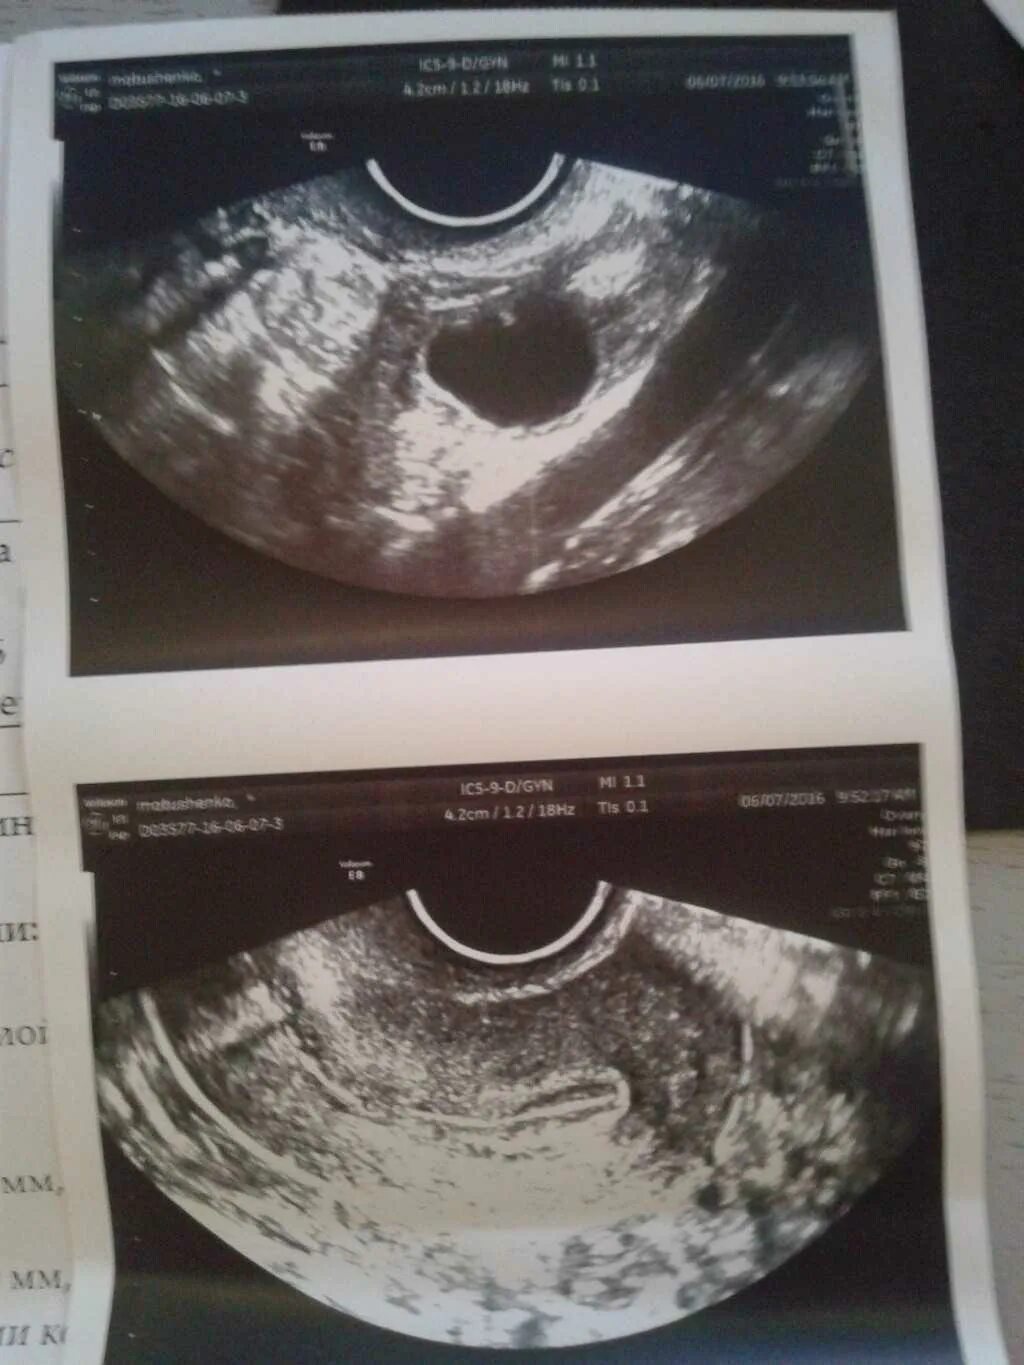

Фолликул 18 мм